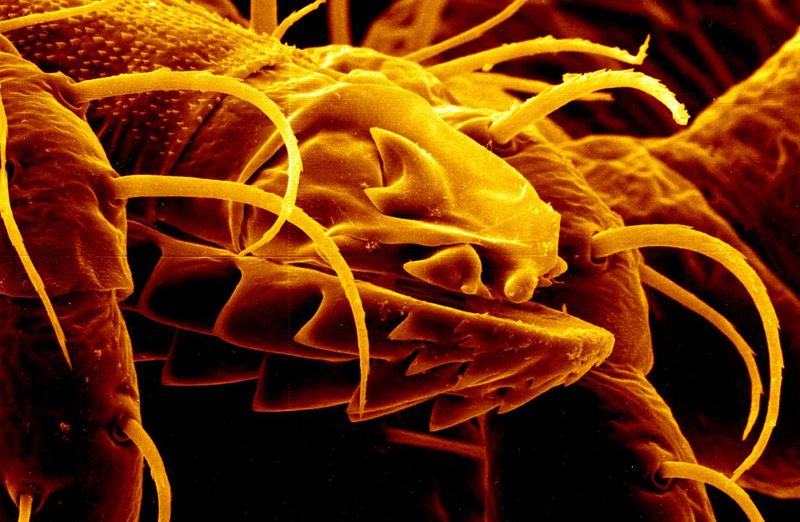

Have you ever wondered what sex would look like if you were able to see INSIDE the bodies of the participants? No? Just me?

The rest of this article is behind a paywall. Please sign in or subscribe to access the full content.Well, even if you haven't wondered, you can now find out.